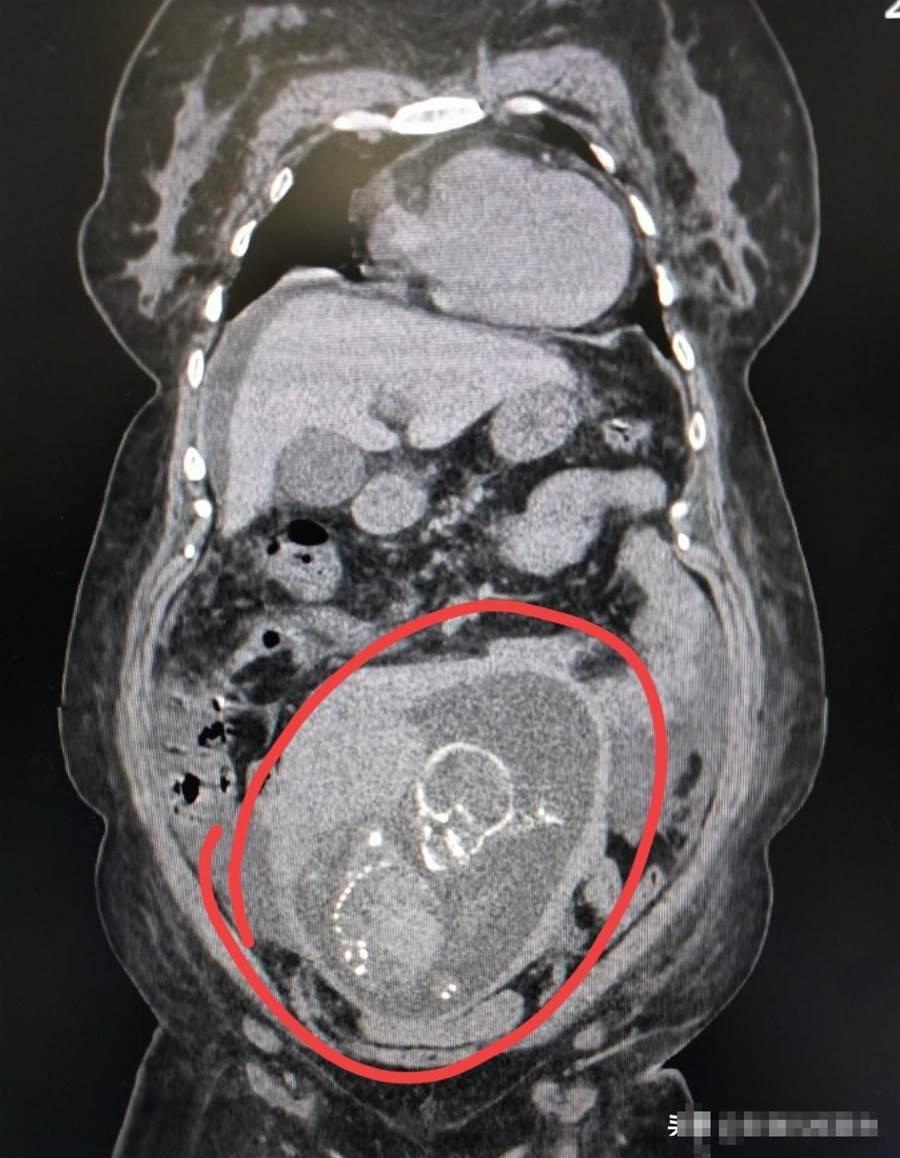

技師按流程擺位、掃描。螢幕一亮,所有人都愣住:宮區內清清楚楚躺著一顆已經成形的小腦袋。技師脫口而出:「您懷孕了?怎麼還來拍CT?」話音未落,李先生臉色瞬間煞白,一把攥住技師胳膊:「什麼孩子?你們是不是看錯了?」